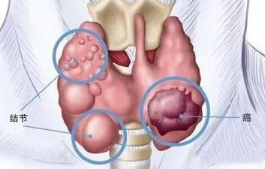

04.体检发现甲状腺上有个结节,是不是癌前病变?

甲状腺结节指的是甲状腺表面或内部生长的团块,比较常见,但大约只有1%的结节为恶性。若体检发现甲状腺结节,不用太过担心,需进一步检查确认是良性还是恶性。